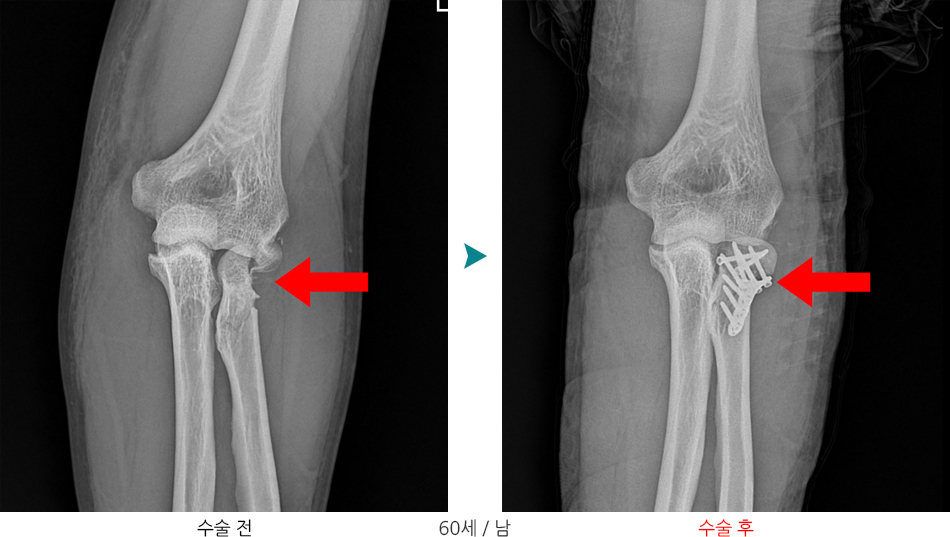

요골두골절과 구상돌기골절이 동반된 주관절 탈구는 주위 연부조직과 골조직에 심한 손상을 주는 복합손상으로 측부인대 손상이나 관절 불안정성이 흔히 동반되며 적절한 치료를 받지 않을 경우 합병증으로 만성관절 불안정성, 관절강직, 이소성 석회화 및 외상 후 관절염등이 흔히 발생하기 때문에 예방을 위해서는 적절한 치료와 재활이 필요하며, 적절한 치료를 받지 못하거나 치료시기를 놓치는 경우 팔꿈치 인공관절 전치환술을 시행해야하는 상태로 이어질 수 있습니다.

※ 각각의 분류형태에 따른 치료방법으로는 1형은 보존적치료, 2형은 관혈적 정복술 후 내고정술, 3형은 요골두 절제술 및 요골두 인골관절치환술을 시행하게됩니다.

1형의 경우 보존적치료를 시행하며, 2,3형의 경우 관혈적 정복술 후 내고정술을 시행하게됩니다.